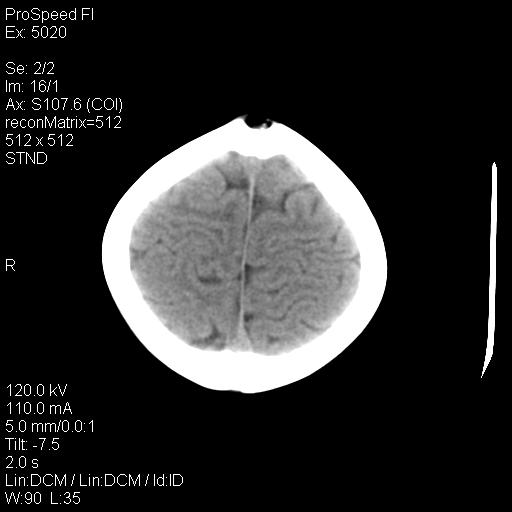

标题: PED1637:M 6Y 顶部无痛性包块两月。 [打印本页]

标题: PED1637:M 6Y 顶部无痛性包块两月。

2、颅骨局部缺失,边缘光滑、整齐

2、颅骨皮样囊肿,皮样囊肿内为脂肪密度ct值多为负值,常在-15~10hu之间。

3、颅骨表皮样囊肿 病灶常有完整的包膜,ct值高低不等,可为脂肪密度至软组织密度,ct值常在-70—120hu之间。

颅骨的病损表现为内外颅骨板层不规则的锋利的破坏,形成“斜边缘”,有一定的特点

颅骨为好发部位,生长缓慢,常位于顶骨、枕骨及颞骨,表现为颅骨缺损,呈圆形或椭圆形,边界清,无硬化

事发冠状缝与矢状缝交界区,密度较低,考虑表皮样囊肿可能性大,其次不除外嗜酸性肉芽肿